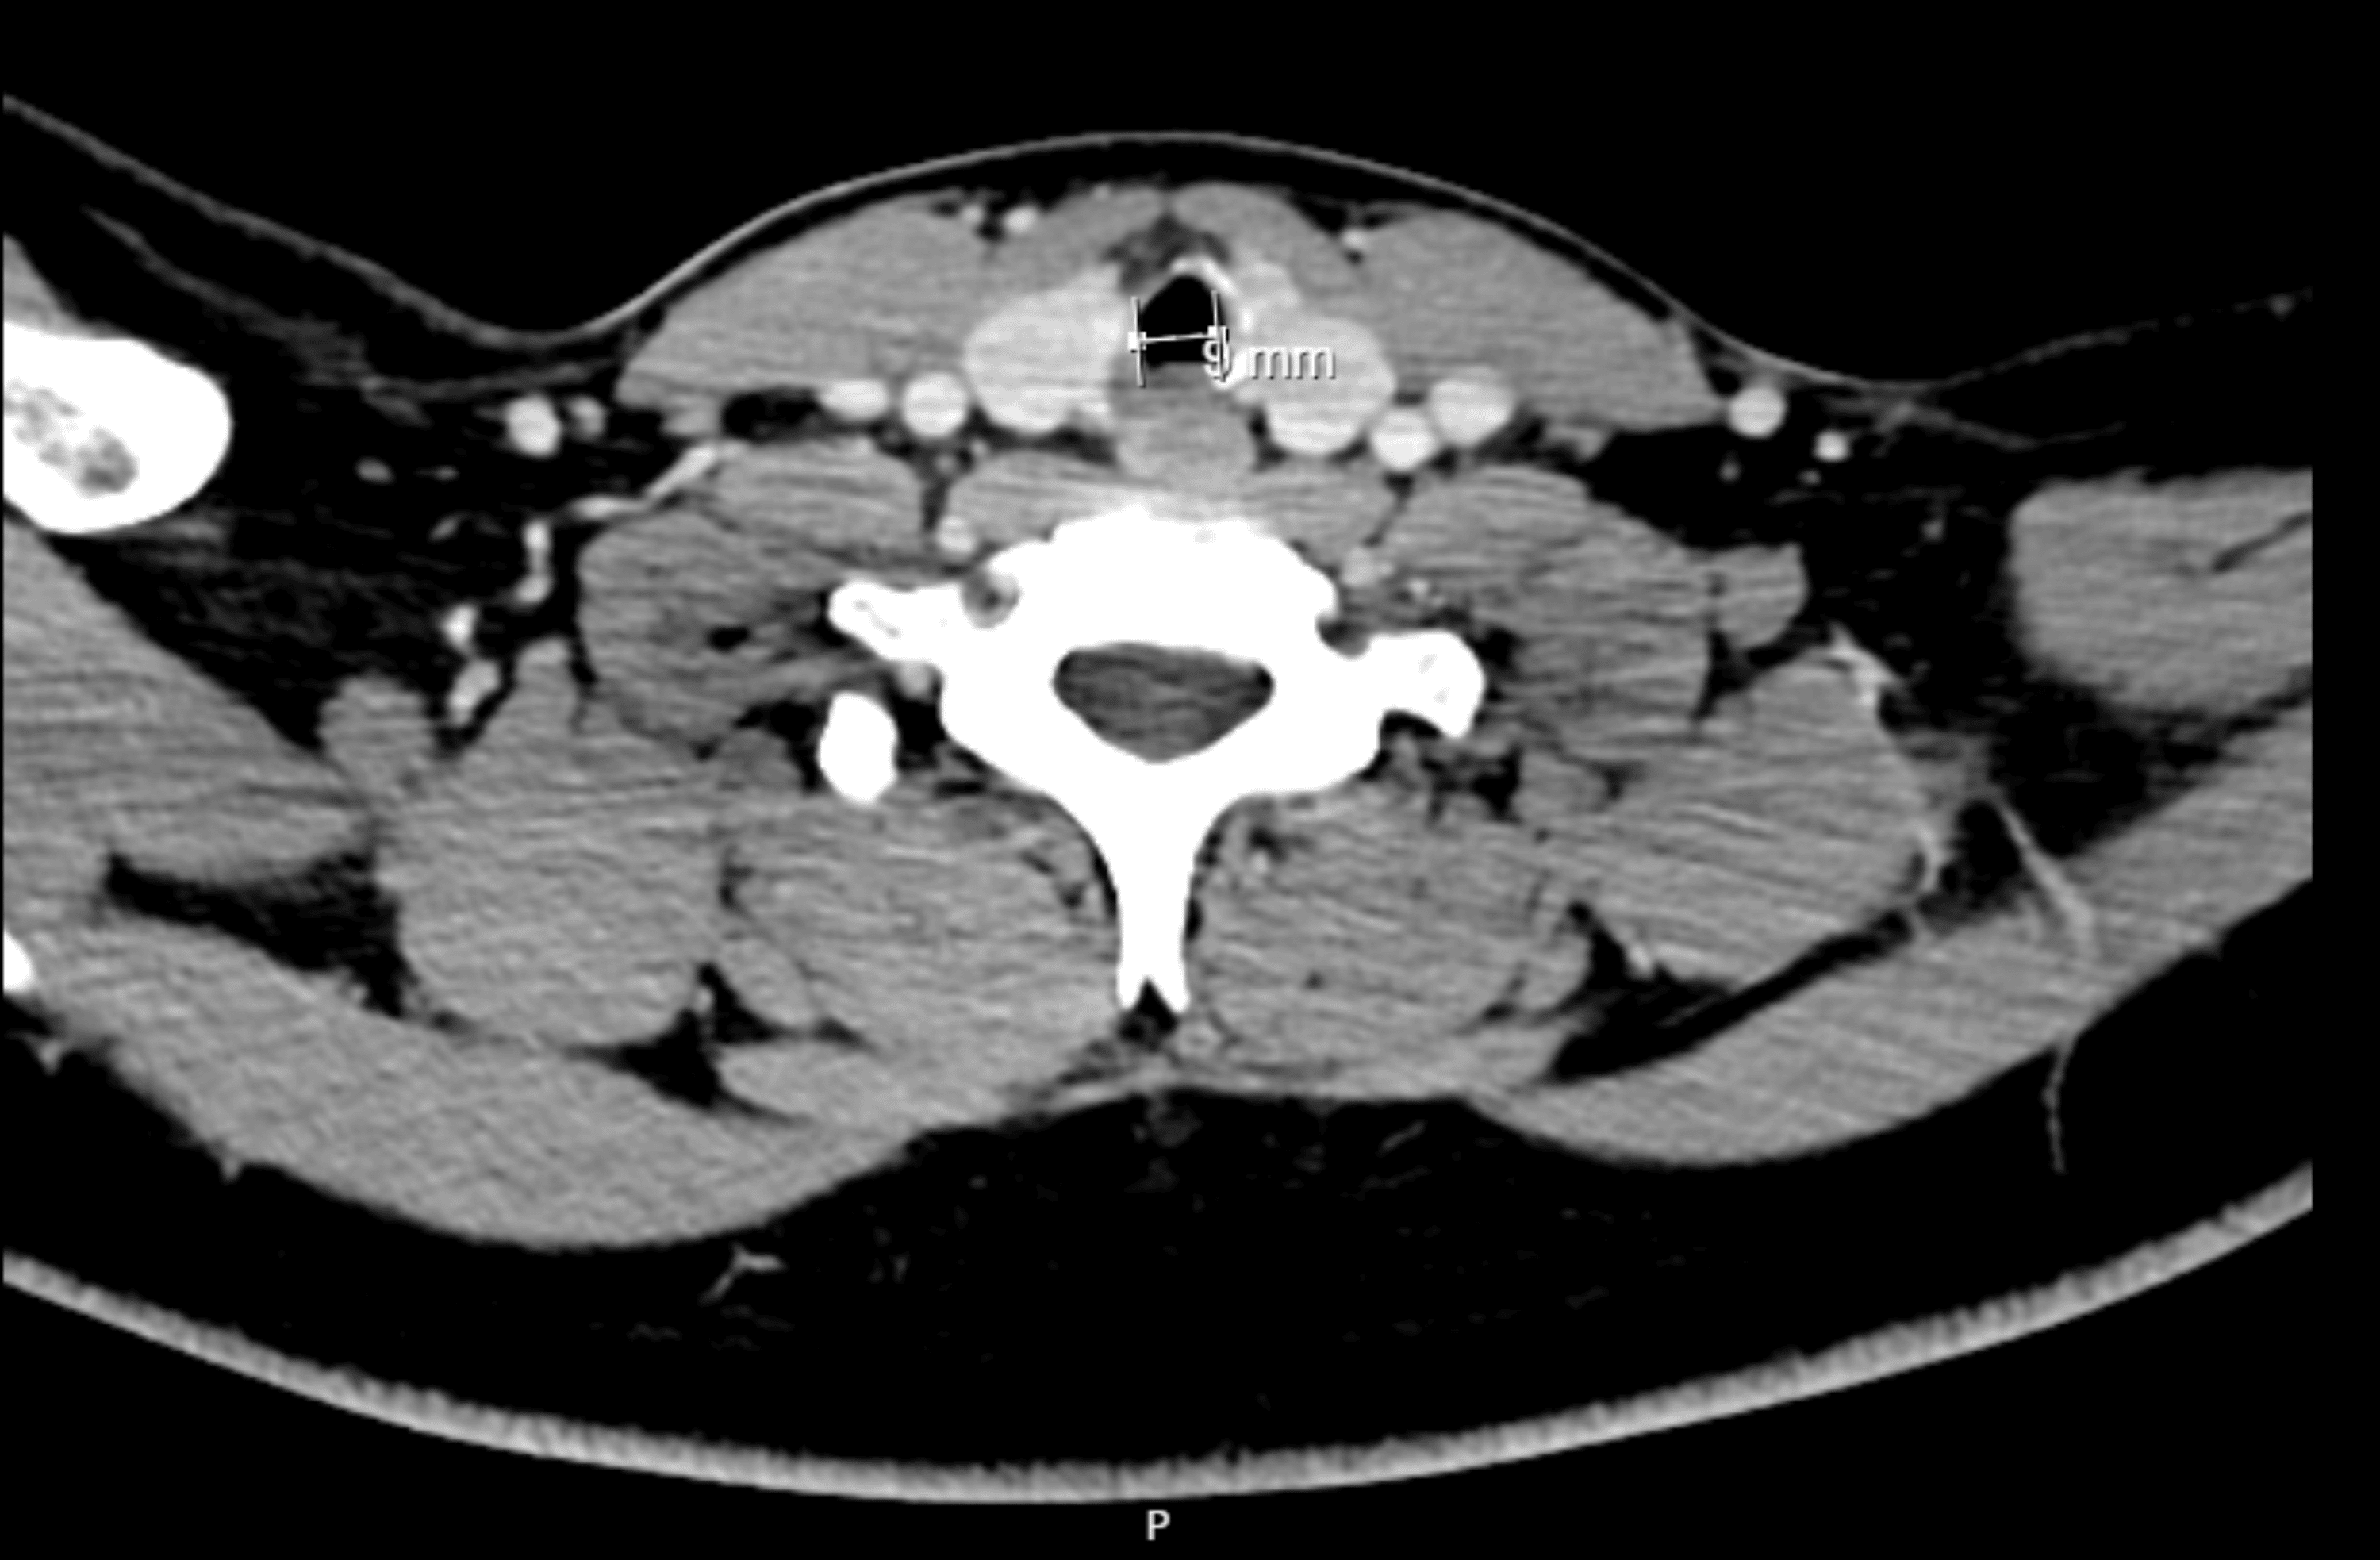

Approximately six months before surgery, he was admitted to a pediatric intensive care unit because of traumatic brain injury with subarachnoid hemorrhage and cerebral contusion. He was under mechanical ventilation/endotracheal intubation for five days, which was the most probable cause for the referred subglottic stenosis. Other relevant previous medical history included Bardet-Biedl syndrome and asthma without recent exacerbations motivating hospital admission. His regular medication included budesonide, formoterol, fenofibrate, and montelukast. He had no medication allergies. Preoperative airway physical examination revealed a grade II Mallampati score, mouth opening greater than 3 cm, thyromental distance of 6 cm, good cervical spine mobility, and a slightly widened cervical perimeter. He mentioned shortness of breath with exertion but during pre-anesthetic evaluation, he was asymptomatic, at rest. Preoperative laboratory results (hemogram, renal function, and coagulation) were unremarkable. Cervicothoracic computed tomography (CT) scan showed a subglottic polypoid formation, 13.5 mm away from the inferior margin of the thyroid cartilage, measuring approximately 3.5 mm in maximum extension and another contralateral polypoid area, very likely consisting of fibrous tissue, with a minimum diameter of 9 mm in the subglottic larynx (Figure 1).